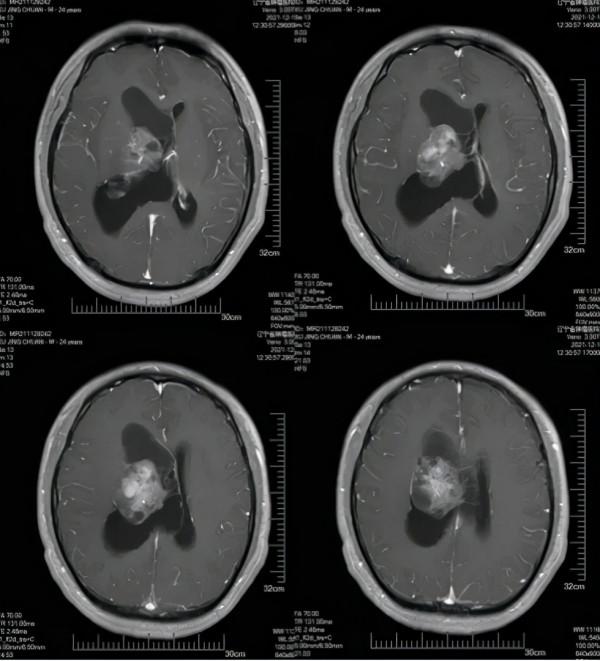

患者,男性,24歲。以“間斷性頭痛5年,加重20日”為主訴入院。診斷為右側腦室內佔位性病變。

術前的增強核磁共振影象中

可見右側腦室內腫瘤,與丘腦粘連緊密

術後CT影象,可見腫瘤切除滿意

患者術後恢復良好